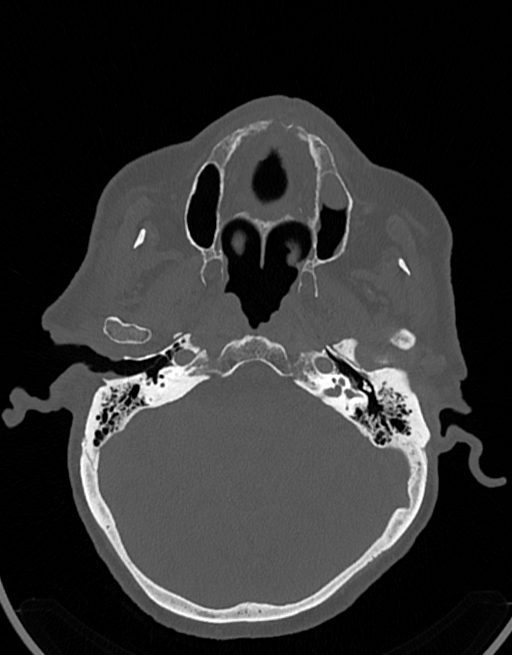

در سي تي اسکن اسپيرال نازو فارنکس با و بدون کنتراست (مولتي ديدکتور 16 با مقاطع ظريف و بازسازي هاي ساژيتال و کرونال):

– توده نسج نرمي به ابعاد mm 40 x 45 x 60 در ناحيه پاروتيد راست، با enhancement هتروژن پس از تزريق کنتراست مشهود است که مطرح کننده آدنوم پاروتيد مي باشد.

– شواهدي از تهاجم توده به استخوان و عروق اطراف مشهود نيست .

– کلسيفيکاسيون در ديواره شريان هاي کاروتيد دو طرف مشهود است .